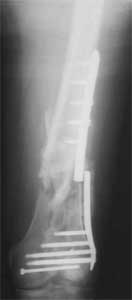

I presented a series of ~25 such cases at EuroTrauma'2004. Many cases were discussed here. I attach am example. Look also recent cases at http://www.hwbf.org/hwb/conf/alex58/scfx.htm,

Did you mark valgus malalignment in that case with LISS you posted Nov 9? Aplication of external distractor can help to avoid the pitfalls but some further development of the technology is necessary to shorten the learning curve.